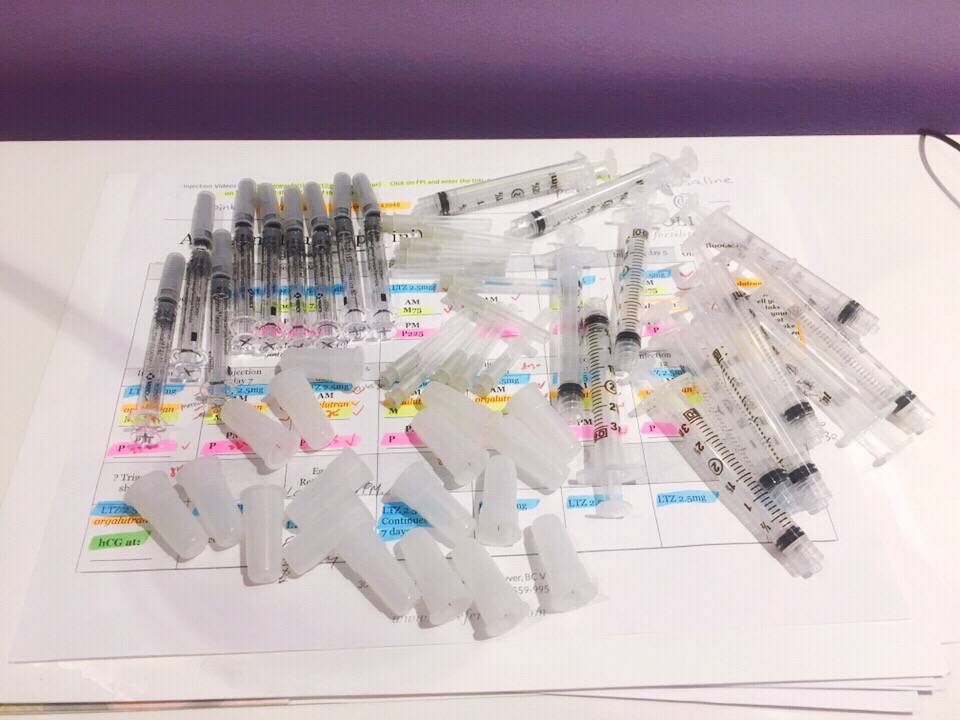

本人女29未婚未育手术前偶尔知道可以冷冻卵子 前提是要在化疗前做大家都知道化疗药物复合卵巢子宫都有一定副作用。一般医生都是建议内分泌药吃五年才可以考虑生孩子 生完继续内分泌五年我自己认为越年轻卵子质量也越好 数量可能也会相对高一点当我五年后34岁 我的卵子还是29岁的状态 而且是未受化疗药物污染的。我觉得为什么不尝试呢以下就来亲说我的取卵过程第一次去咨询的时候做了阴超显示可能有15颗左右卵子第二次是月经来的第二天 又检测了一下卵子 查了血接着自己回家打menopur 75IU ➕ purogan 225IU 每天还要吃一颗来曲挫到第五天的时候去诊所验血 下午通知加打一针orgalutran 接下来的10天左右都是每天定点自己在肚子上打三针 最后五天开始每天检测卵泡大小是否超过17mm到了周一终于不用再打针了 因为周二可以取卵了我没有做全麻 首先做椅子上吃了止痛药 放松的药 还有打了头孢。时间差不多就走去手术室 准备手术术前医生先帮忙清洗下体感觉跟生孩子差不多的姿势 也不知道他弄了些什么 不痛 就是这时候开始打麻药了 有点晕接着正式开始手术 就看到屏幕里一根针插入卵泡把它慢慢吸走 接着换另一个卵泡接着吸一共吸了十分钟 就被告知手术结束了腿上轮椅回到休息室休息了一个小时 并且打了点滴 才让我不那么晕也不想吐了 回家接到电话 取出22枚卵子。成熟的可以冷冻的有9颗好吧虽然一残都没到。但我多了一条后路哪天想生孩子 至少我还有年轻且健康的卵子存在想想心里也舒服点不是么附上我这两周自己给自己打的针 还有最后那些黑黑的球球就是卵泡😁